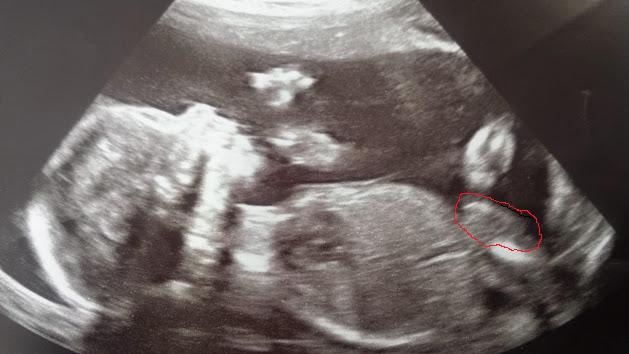

Attachment 22442Attachment 22443

Some more pictures. The first is another from 20 weeks and the second it 11 weeks 2 days